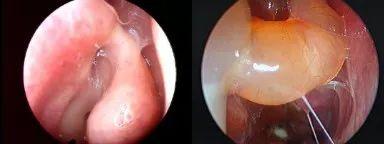

图1中鼻道息肉

图2 治疗后

1、内镜检查:来源于中鼻道、嗅裂的黏脓性分泌物,中鼻道粘膜充血、水肿或有鼻息肉。

2、影像学检查:CT扫描显示窦口鼻道复合体或鼻窦粘膜病变。